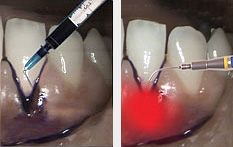

Лазерный кюретаж или антибактериальная фотодинамическая терапия (ФДТ) в странах Европы успешно применяется для лечения пародонтита уже более 15 лет. В результате лечения методом ФДТ любых форм хронического пародонтита достигается стабильный продолжительный эффект.

Лечение пародонтита методом ФДТ происходит по простой схеме:

Огромным преимуществом использования данного метода лечения пародонтита является то, что разрушается только патогенная флора, на здоровые ткани лазер и фотосенсибилизатор никакого влияния не оказывают. В результате антибактериальной фотодинамической терапии пораженные участки периодонта обретают защиту в виде фотокоагуляционной пленки, которая не допускает попадания бактерий и способствует скорейшему закрытию зубодесневых карманов.